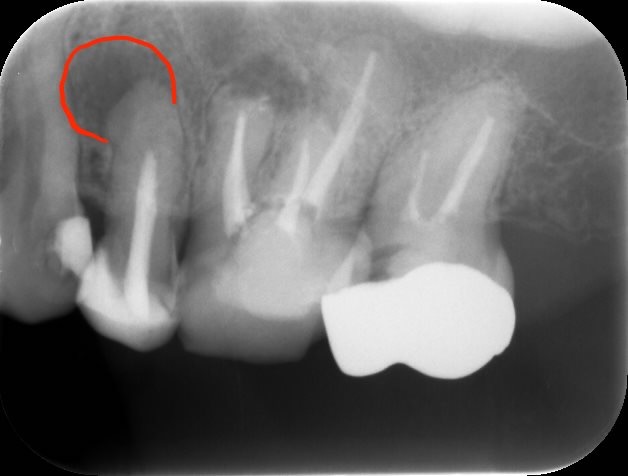

治療前レントゲン

術前レントゲン

レントゲン上で、左上5番目に歯の根の先に黒い透過像(赤い丸)が認められ、叩いた時の痛みなどの検査から、患歯が特定できましたので、根の治療(根管治療)を行うことになりました。